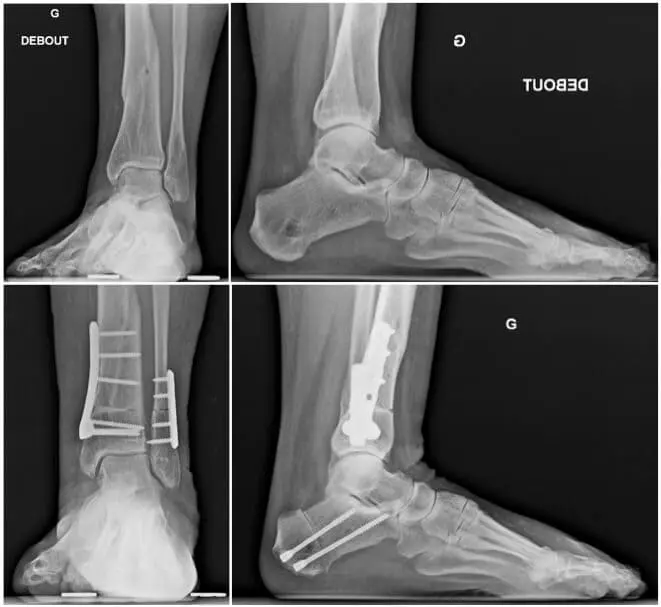

- Supramalleolar and/or calcaneal osteotomy: when a joint is not parallel to the ground, and only affected by this misalignment on one side of the joint, we can propose a supramalleolar and/or calcaneal osteotomy. The aim is to bring the gravity force and other forces involved around this joint back into balance and to let them pass onto the main and still healthy part. This is, in very specific cases, well worth doing and it may win some years before having to switch to an arthrodesis or a prosthesis.